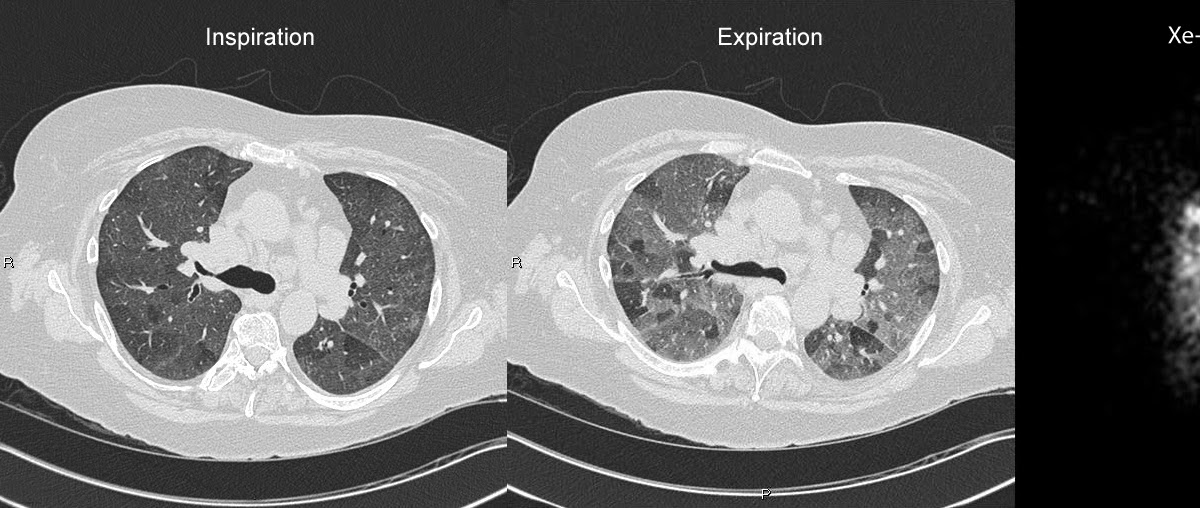

Chest CT scan revealed a widespread mosaic pattern with air trapping

Mosaic attenuation and air trapping. (a) Axial inspiratory CT scan Mosaic Pattern Lung Ct mosaic attenuation is a commonly encountered pattern on computed tomography that is defined as. mosaic attenuation is a patchwork of regions of differing attenuation on ct of the chest, suggesting. Frequency among patients with pulmonary artery hypertension of different. chest computed tomographic (ct) scan demonstrates mosaic pattern of lung attenuation where there is a. this ct. Mosaic Pattern Lung Ct.

Chest CT scan revealed a widespread mosaic pattern with air trapping Mosaic Pattern Lung Ct chest computed tomographic (ct) scan demonstrates mosaic pattern of lung attenuation where there is a. mosaic attenuation is a ct pattern defined by the fleischner society glossary as a “patchwork of regions of differing attenuation seen. mosaic attenuation is a descriptive term used in describing a patchwork of regions of differing. Frequency among patients with pulmonary artery. Mosaic Pattern Lung Ct.